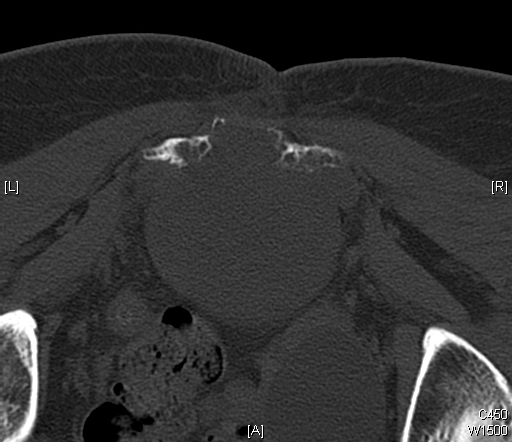

CT (Fig. 11 & 12)

• Destructive bone lesion

• Cortical destruction

• Soft tissue mass is easily detected on a CT scan

• 20% of patients with chordomas shows calcifications

• Subtle calcification are easily detected with CT scan

Fig. 11 & 12: CT scan of a sacral chordoma demonstrates a lytic lesion of the sacrum with a soft tissue mass. Subtle calcifications in the axial CT scan.